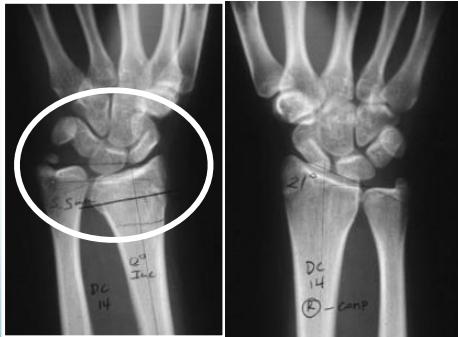

Injury films

Case Example: 12-year-old male, Salter-Harris Type II